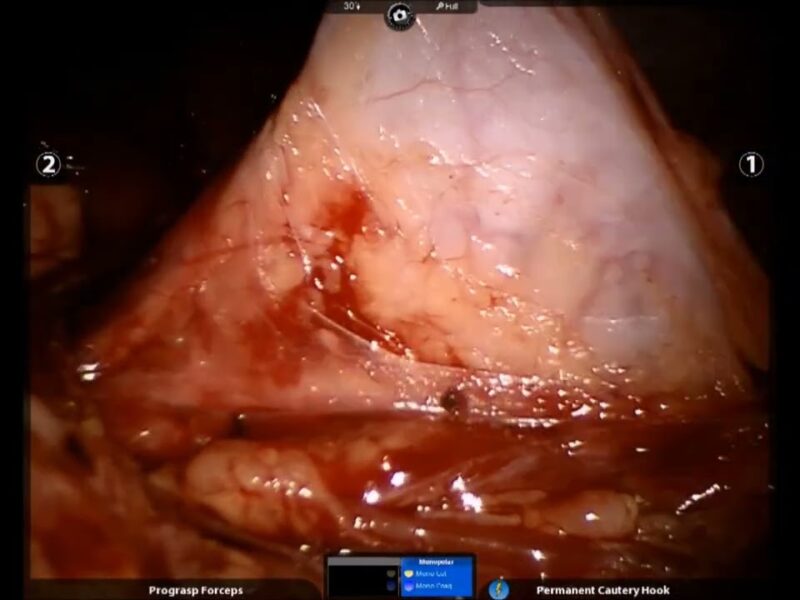

551 Handheld robotic arm assisted vaginal hysterectomy

Dr. Suyash Naval

The vaginal route is considered best to do a hysterectomy. However, the large size of the uterus poses a unique problem that significantly increases the difficulty of transvaginal hysterectomy due to less operative space and poor vision. In recent years, vaginal natural orifice transluminal endoscopic surgery (vNOTES) has evidently helped to overcome these difficulties. But vNOTES involves the use of straight-stick laparoscopy instruments that can clash during surgery, as this approach is similar to single-port surgery. Therefore, we propose an innovative solution of using a novel handheld robotic arm for assistance in vNOTES hysterectomy for difficult cases. A handheld robotic arm has a significantly smaller size compared to a full console multiple-arm robotic system. Moreover, it does not require docking. Although a handheld robotic arm does not have all the attributes of a multi-arm robotic system, the aforementioned advantages possibly make it more convenient in the vNOTES setting. Gynecology, New Technology